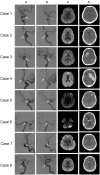

Background: We sought to analyze diffusion-weighted imaging (DWI) and dual antiplatelet therapy (DAPT) for risk factors of delayed intracerebral hemorrhage (d-ICH) after coil embolization for an unruptured intracranial aneurysm (UIA). Methods: A total of 539 aneurysms were analyzed in this study. Ruptured and flow diverter cases were excluded. All aneurysms enrolled in this study were treated with stent-assisted or simple coiling techniques. Before the procedure, all patients administered (DAPT). After the procedure, patients who underwent stent-assisted coil embolization were given DAPT, and patients who underwent simple coiling were given single antiplatelet therapy (SAPT) only during their admission. The response of the antiplatelet agent was assessed the day before the procedure with The VerifyNow assay. DWI MRI and CT were obtained routinely the next day after the procedure. d-ICH was defined as an intracerebral hemorrhagic lesion identified in follow up CT at least 48 h after the procedure. Results: A larger positive lesion on day 1 DWI MRI (p = 0.001), the value of PRU (p = 0.002), and the inhibition rate (p = 0.025) were considered meaningful risk factors for d-ICH in univariate analysis. Accordingly, larger DWI positivity (OR = 83.73, 95% CI = 11.132-712.886, P = 0.001) and PRU (OR = 0.98, 95% CI = 0.972-0.999, P = 0.033) reached statistical significance in multivariate analysis. Conclusions: Thromboembolic infarction may work as an initiating factor, and antiplatelet medication may work as an aggravating factor. We might suggest that a tailored reduction in antiplatelet agents could help reduce d-ICH when a larger volume of post-procedural thromboembolic infarction is seen on 1-day follow-up DWI MRI.

Figures